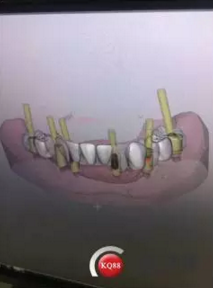

1)術(shù)前檢查,拍攝臨床照片及CBCT檢查,制取活動(dòng)義齒參考模型,指導(dǎo)后期最終修復(fù)的牙齒排列

2)術(shù)前準(zhǔn)備及手術(shù)過(guò)程,測(cè)量血壓及血糖,簽種植知情同意書;嚴(yán)格遵循無(wú)菌操作,局麻下采用微創(chuàng)技術(shù)于323436分別植入osstem4.0X10,4.0X10,4.5X7; 434446分別植入osstem4.0X1O,4.0X10,4.5X7.初期穩(wěn)定性均達(dá)到了35N.CM以上;嚴(yán)密縫合,止血,種植體位點(diǎn)和方向與設(shè)計(jì)一致。

6)數(shù)字化義齒制作中心制作完成修復(fù)體臨時(shí)冠橋試戴,合適后完成最終二氧化鋯橋修復(fù)體